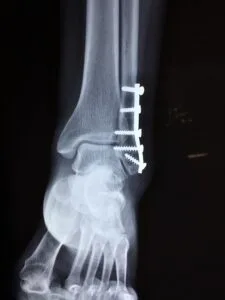

An ankle sprain can be characterized by lateral ankle pain, swelling, and instability. A stress X-ray may be useful in diagnosing fractures.